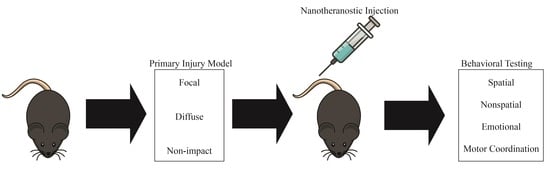

5.6. Penetrating Ballistic-Like Brain Injury

5.7. Controlled Cortical Impact